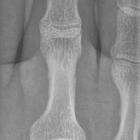

Interphalangealgelenk Großzehe; oben luxiert, unten nach Reposition.

dislocation of the interphalangeal joint of the hallux (big toe).